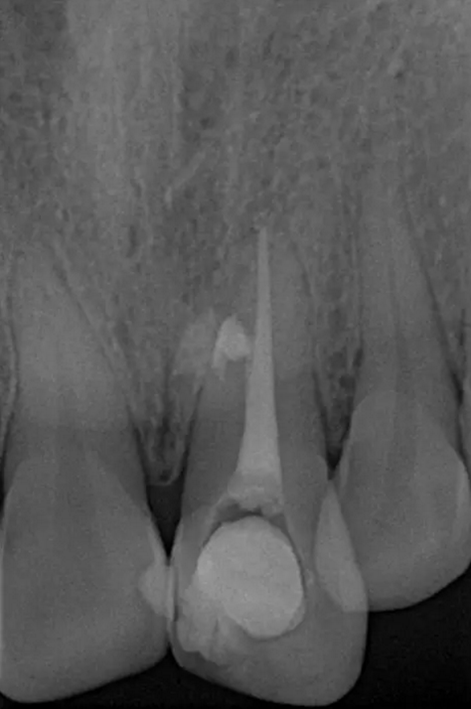

患者女,年齡35左右,牙位21,根管治療曾經(jīng)歷過外院四到五次等不同地方的處理,還是不能咬硬物,會有酸、軟、痛的情況出現(xiàn),偶有自發(fā)疼痛,2016年9月初,轉(zhuǎn)診至我處治療21。術(shù)前拍片發(fā)現(xiàn)根中部存在側(cè)穿,橡皮障下常規(guī)再治療,隨后減輕了軟和痛的情況。因為側(cè)穿,牙周膜受到牙膠尖等異物的持續(xù)刺激,酸軟的情況還是持續(xù)存在,所以決定行根尖外科手術(shù),采用MTA修補穿孔點。術(shù)后觀察半年左右,所有癥狀消除后,隨后熱牙膠充填。

術(shù)前診斷片